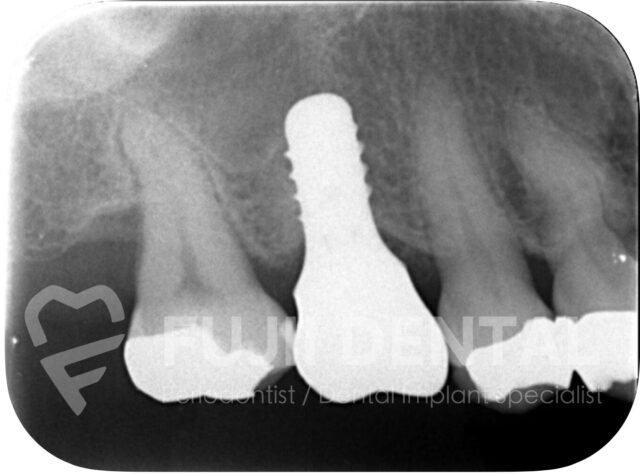

最終的な補綴物(被せ物)を装着した状態です。8mmあった歯周ポケットは正常値の3mmへと治癒し、抜歯と手術回数を最小限に抑えながら、歯周病を治し、しっかり噛める状態を回復しました。

- 通常1年程度かかる治療を、約半年で完了

- 本来3〜4回に分けて行う外科処置を、2回で完結

- 切開を最小限に抑え、歯周ポケットを確実に改善

- 抜歯を1本に抑えることで、治療期間中も残した歯で噛める状態を維持